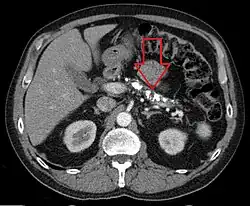

Axial CT showing multiple calcifications in the pancreas in a patient with chronic pancreatitis

Computed tomography, magnetic resonance cholangiopancreatography (MRCP), and endoscopic ultrasound (EUS) all have similar sensitivity and specificity for diagnosing chronic pancreatitis.[3] MRCP is particularly utilized for its sensitivity in imaging the pancreatic ducts and bile ducts for associated changes such as stones or strictures.[3][12] A biopsy of the pancreas is not required for the diagnosis.[3] On imaging, pancreatic and bile duct dilatation, atrophy of the pancreas, multiple calcifications of the pancreas, and enlargement of pancreatic glands can be found.[12]